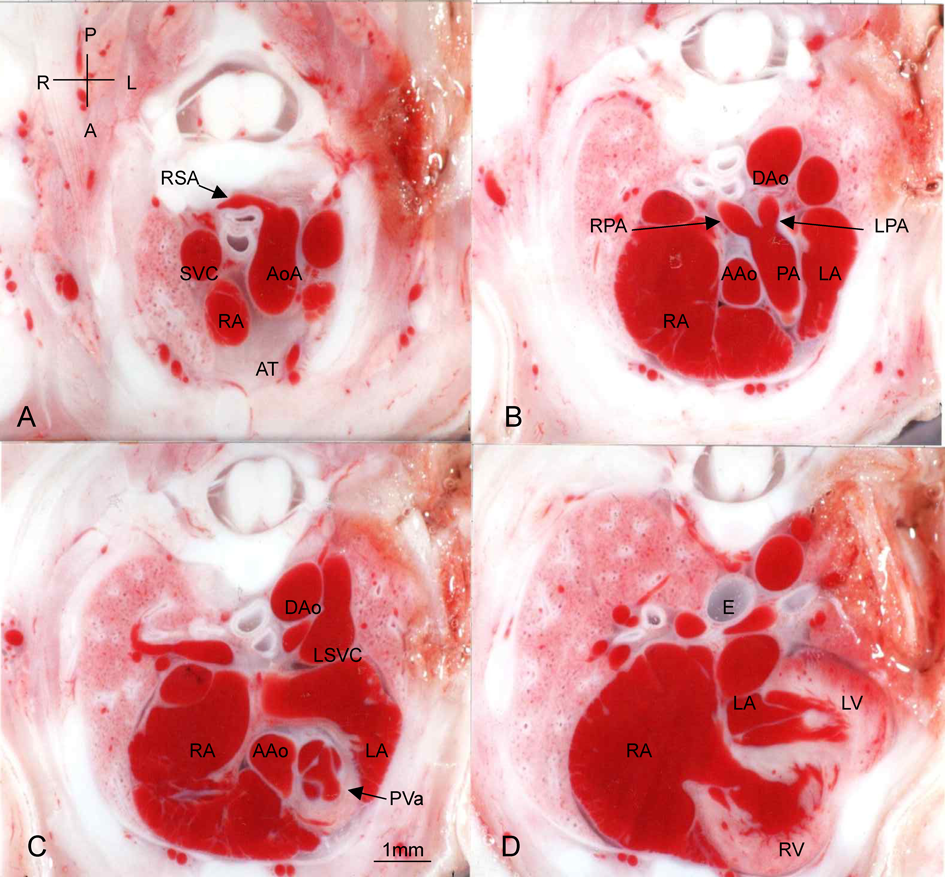

Fig. 1 Normal heart with aberrant RSA (A) and absent thymus (A). Transverse section.

Abbreviations in figures 1 to 6. A, anterior; Ao, aorta; AAo, ascending aorta; AoA, aortic arch; AoV, aortic valve; AORSA, aberrant origin of RSA; AT, absent thymus; AVV, atrioventricular valvel; B, broncus; Ca, caudal; Cr, cranial; DA, ductus arteriosus; DAo, descending aorta; E, esophagus; IVC, inferior vena cava; L, left; LA, left atrium; LBCA, left brachiocephalic artery; LCCA, left common carotid artery; LPA, left pulmonary artery; LSVC, left superior vena cava; LV, left ventricle; P, posterior; PA, pulmonary artery; PV, pulmonary vein; PVa, pulmonary valve; R, right; RA, right atrium; RCCA, right common carotid artery; RPA, right pulmonary artery; RSA, right subclavian artery; RV, right ventricle; SVC, superior vena cava; T, trachea; TA, truncus arteriosus; TAr, truncal arch; Th, thymus; TV, truncal valve; VSD, ventricular septal defect.

Fig. 1では先天性心疾患なく,右鎖骨下動脈起始異常,胸腺欠損が認められる.